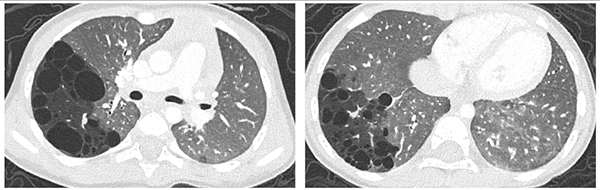

症例3は,80歳代,女性,関節リウマチ・シェーグレン症候群に伴う間質性肺疾患の症例である。4年前の従来CT(図5 a)にて,網状影や比較的囊胞サイズの大きな蜂巣肺の陰影が認められるが,NAEOTOM Alpha(図5 b)ではより微細な構造が描出されている。また,FOVを200mmに設定した1024マトリックスの画像(図5 c)では,微細な構造の視認性がさらに向上している。PCD-CTは,通常型間質性肺炎の評価に有用であることが文献でも報告されている4)。

図5 症例3:間質性肺疾患症例における微細構造の視認性の向上